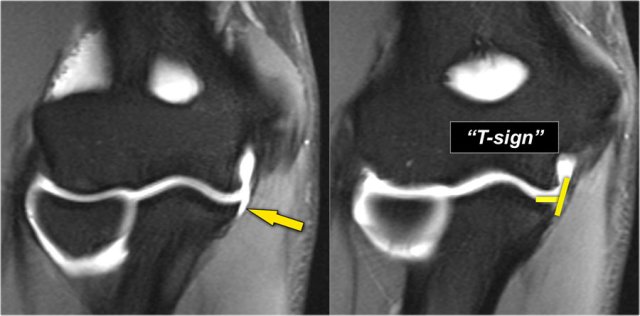

This is a 18 year old baseball pitcher with medial elbow pain.

A partial tear is seen creating a 'T-sign'.

First study the coronal T2-fatsat images and then continue reading...

Notice that the anterior bundle is intact and firmly attaches to the sublime tubercle (yellow arrow).

On the next two images there is some soft tissue edema and more abnormal signal posteriorly (red arrow). So we suspect pathology of the posterior bundle.